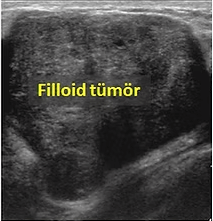

Filloid Tümörleri ​

Klinik olarak, filloid tümörler memenin iyi huylu bir tümörü olan fibroadenomlarla karışabilirler. Ultrason, mamografi ve MR ile bu ikisini güvenilir bir şekilde ayırmak mümkün değildir. Ancak, fibroadenomlar 20-30 yaşlarında, filloid tümörler ise 40-50 yaşlarında daha sık görülürler. Ayrıca, filloid tümörler, fibroadenomlara göre çok daha hızlı büyüme gösterirler. Bazı filloid tümörler birkaç hafta içinde 2-3cmlik boyuta ulaşabilirler. Sonuç olarak, ultrasonda fibroadenom zannedilen bir kitle eğer hıuzlı büyüme gösterirse filloid tümör akla gelmeli ve kitleden kor (trukat) biyopsi yapılmalıdır.